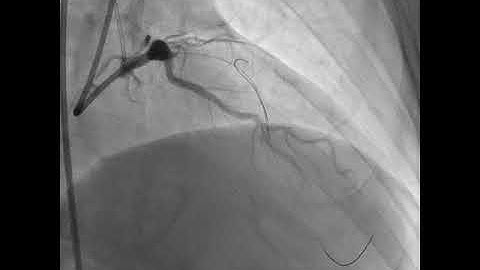

Guide Wire Algorithm Video: Dr. Armstrong BTK Wire Selection Strategy (US)